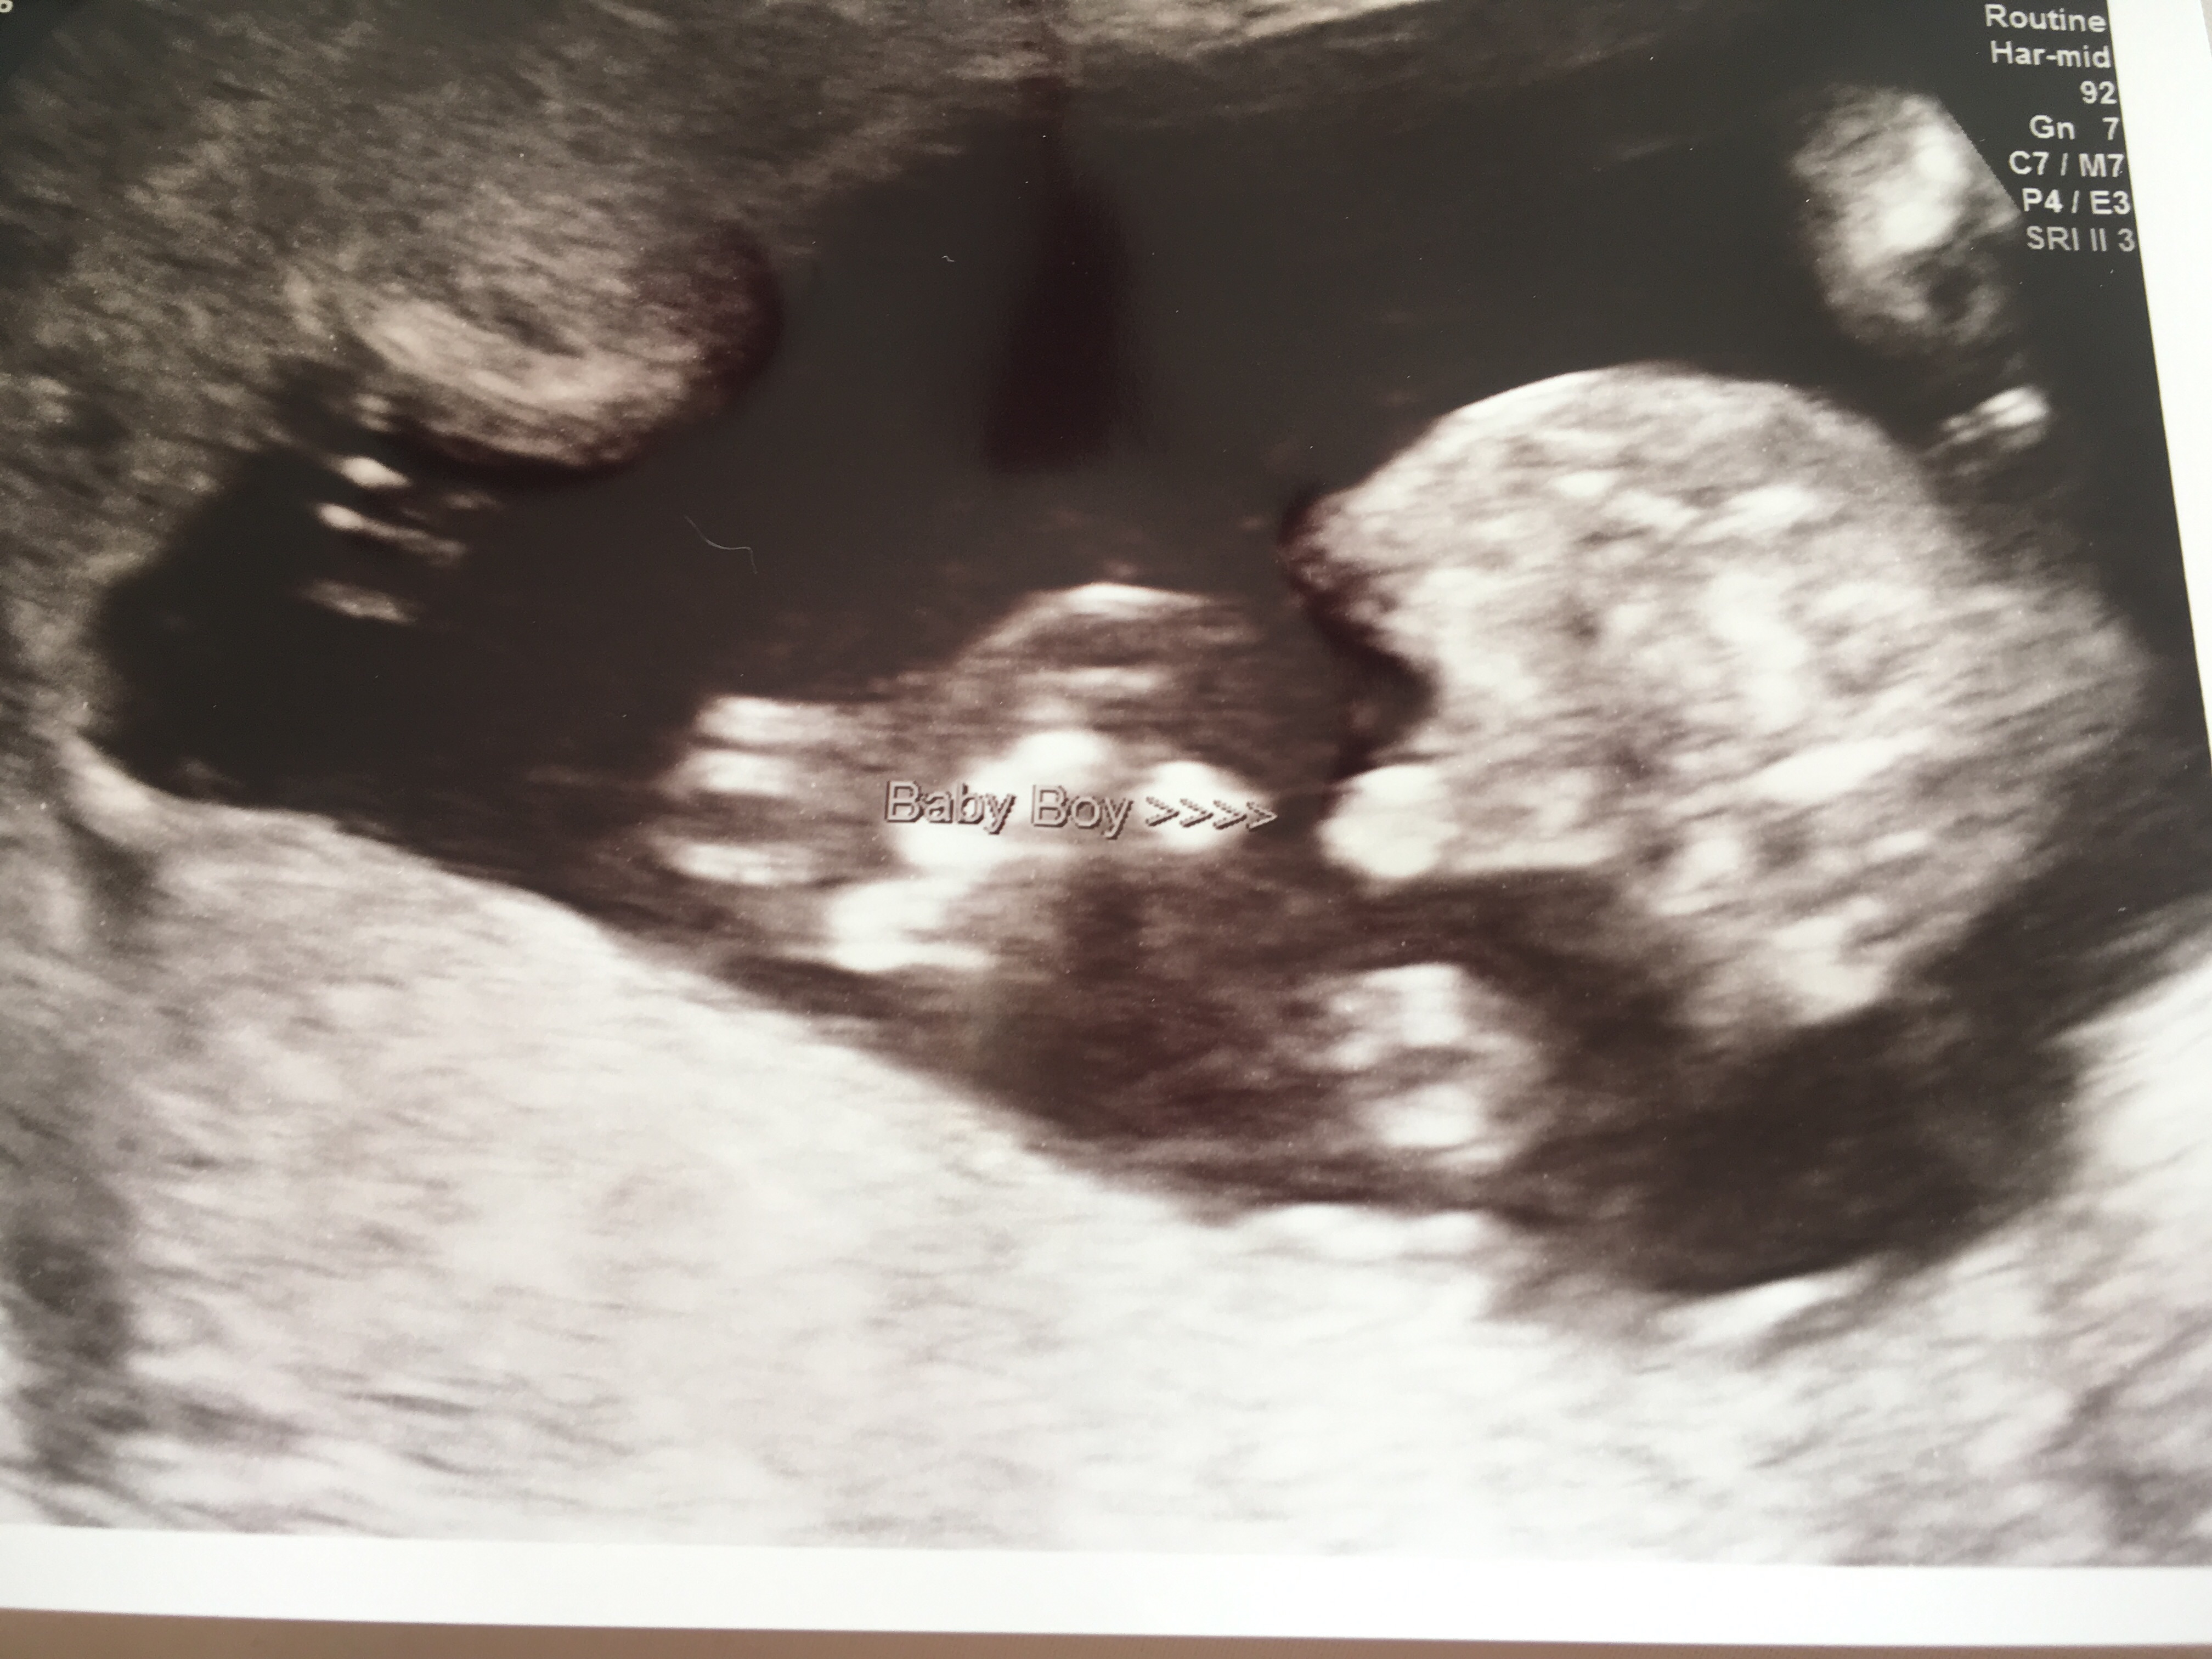

Had a private scan today looks boy tech was certain. Baby was not in great position and kept legs closed. Is there any way this isn’t a boy do you think?! Would it be very obvious now at nearly 17 weeks?

Hmmm. I guess you were hoping girl. I've done ultrasound and I have seen all my five boys. At that week if a tech says it, they are usually pretty sure. Mostly 15 weeks it gets accurate. It does look like a boy but if the tech was really unsure of the sex then I dont know. Let's hear what others say.

That does look like a boy. I'm sorry it's not what you were hoping for.

Yes, that looks boy to me. I'm so sorry it didn't go the way we hoped. But he is absolutely beautiful and I want to congratulate you on your new son. :heart: